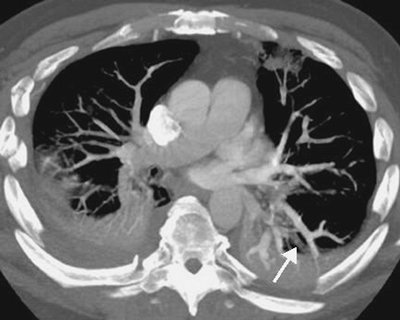

FIGURE 17-8. Acute PE associated with pulmonary arterial hypertension. A: CTPA of a 23-year-old man involved in a motor vehicle crash shows a saddle embolus straddling the right and left main pulmonary arteries (arrows). The central pulmonary arteries are enlarged. B: CTPA at a more inferior level shows thrombus within segmental branches of the lower lobe pulmonary arteries (arrows). C: CTPA at a level inferior to (B) shows leftward bowing of the interventricular septum (arrow).